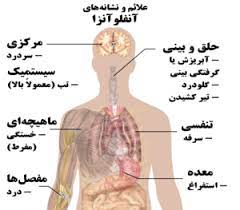

قیمت: 58٬000 تومان - دسته بندی فایل: علوم پزشکیپاورپوینت آنفولانزا

فروش ویژه پاورپوینت حرفه ای آنفولانزا با تخفیف استثنائی ... دسته بندی: پاورپوینت نوع فایل (.ppt) PowerPoint (قابل ویرایش و آماده پرینت) تعداد اسلاید :75 اسلاید